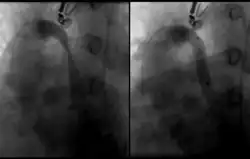

Die zuverlässigste Untersuchungsmethode um CCSVI festzustellen ist eine Katheter-Venographie. Allerdings ist diese mit einem relativ hohen Aufwand an Ressourcen verbunden und bringt für den Patienten eine nicht unerhebliche Strahlenbelastung mit sich. Deshalb wird in aller Regel davor eine Voruntersuchung mittels Magnetresonanz-Venographie sowie eine extra- und transkranielle Doppler-Sonographie[1] durchgeführt. Nur falls diese Voruntersuchungen einen hinreichenden Verdacht auf pathologische Veränderung der Venen geben, wird anschließend die Katheter-Venographie durchgeführt.

Es gibt keine unabhängigen wissenschaftlichen Belege einer positiven Wirkung der aktuell bei CCSVI praktizierten Therapieoptionen. Gegenwärtig wird versucht, mittels Ballondilatation die Verengungen der Venen zur beseitigen.[22] Die Studie zeigte aber auch, dass der Erfolg der Behandlung, je nach Ursache und Lage der Stenosen, teilweise nicht von Dauer war. In problematischen Fällen wird an manchen Operations-Zentren die Implantation eines Stents erwogen, um die Vene dauerhaft offen halten zu können. Das Risiko einer erneuten Verengung der Venen ist in den Jugularis-Venen signifikant höher als in der Vena azygos.[22]